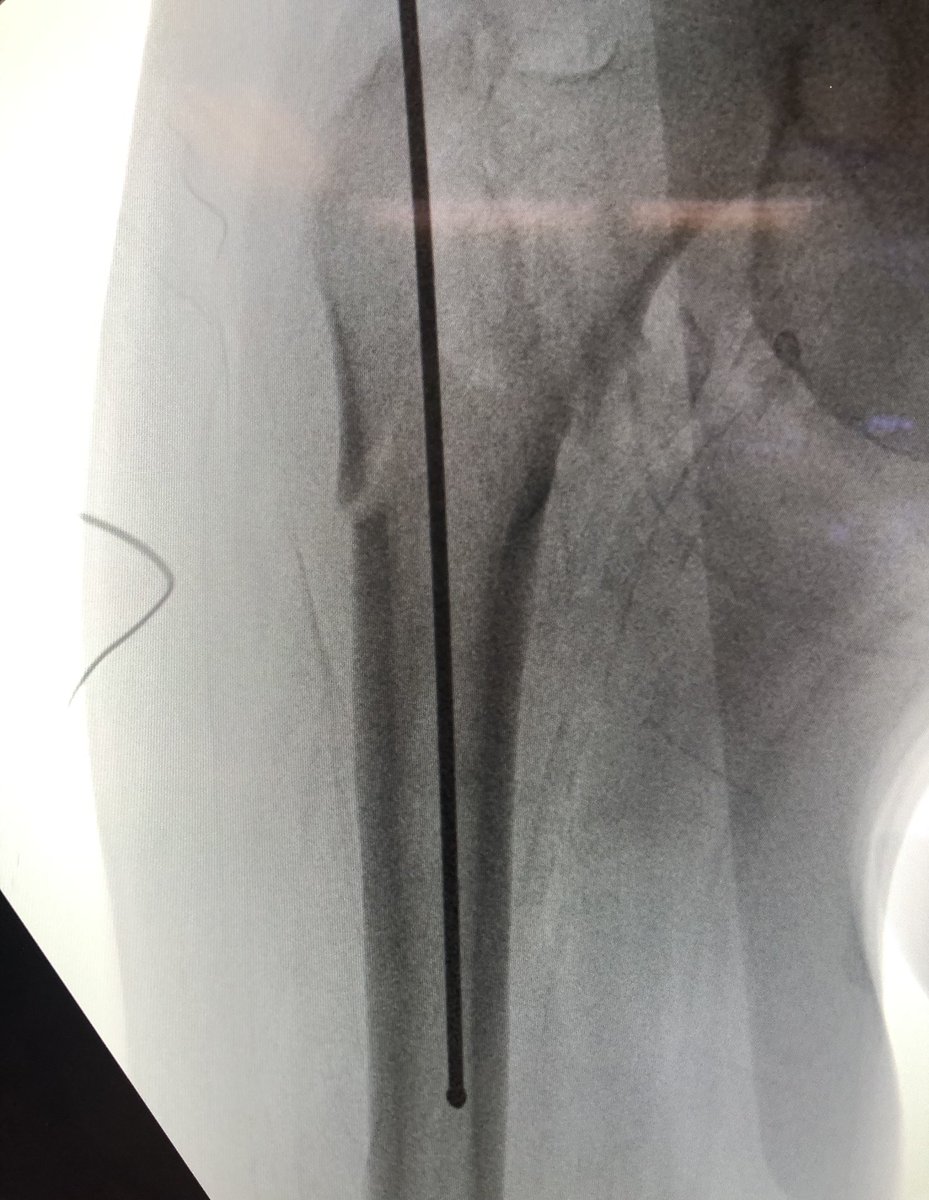

[1/18] Kicking off the new year with some tips of how I do a short cephalomedullary nail for an intertrochanteric fracture. The cases I use here are not all the same and aren’t always “perfectly done” but I try to showcase the best example of the technique itself.

[5/18] Most important: starting point. I draw horizontal line on top of greater troch (green), and hold guidewire up to leg to line up with center of head/neck on perfect lateral & draw line (blue). Stab Incision about 4 finger-breadths proximal / 1 FB anterior to cross of lines.

[6/18] If original start point isn’t good, I leave wire in so new wire doesn’t keep falling into same hole. Also I gently tap to get a foothold instead of using driver so that I can make minute redirections in either plane (yellow). ONLY when I’m happy, I extend stab incision.

[7/18] Once I’m happy with direction, I switch to driver, drive guidewire in metaphysis, then stop and gently tap again. I look for the guidewire to “bounce” off the medial cortex, ensuring it is in bone (not in fracture) and obviating having to go back to the lateral to check.

[8/18] I nearly always use a 10 nail (data to support). It should advance with every whack of the mallet. If it doesn’t, you need to stop and get a long guidewire and ream it out. I’ve seen iatrogenic fractures otherwise.

[9/18] This is where the drawn line comes into play. When you put jig in, you line it up with that line (blue) so that sleeves for the cephalic screw go directly on it. Keep gentle hold on jig (yellow) to keep it from sagging. This way, screw will be close to perfect trajectory.

[11/18] I bring wire up to about blue level (I also like to stay inferior, yellow) in order to see it on lateral. Be sure to remove impactor (metal) otherwise will get in way of visual. If I need to change adjustment on lateral, I drill in reverse & redirect wire also in reverse.

[12/18] To see head well, the c-arm has to be sufficiently “wagged” proximally (yellow). Usually that solves most of my problems with lateral. My angle is about 75 deg from vertical in the other plane, to make up for the usual 15 degrees of anteversion (not quite a full lateral).

[13/18] When drilling/inserting screw, I usually do it on fluoro, I don’t just rely on the stopping point of sleeves because sometimes you can drive guidewire into pelvis. Also wire can come back out with drill so you need to be ready with obturator or another wire to stop it.

[14/18] If you line up screw handle with the line of the femur (blue) your screw end will be in the right plane. If it’s a left hip (clockwise screwing can flex the proximal fragment) I also build in an extra turn to derotate the proximal fragment if needed.

[15/18] I always try to build in some compression. The place to watch is the inferior medial portion of the fracture (arrow). Don’t overdo it or the nail starts to migrate medially.

[18/18] The troch fragment is little abducted here, I don’t worry so much about screw being close to fracture line because nails don’t rely on lateral wall to work. Keep TAD (or calTAD as I do) small and most ITs heal without an issue. I also don’t use blades. Thanks for reading!